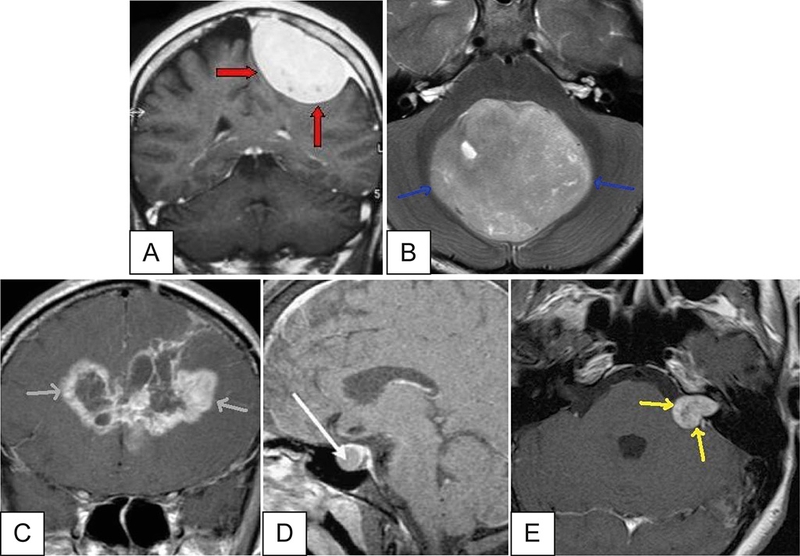

Tìm hiểu về các các loại u não phổ biến hiện nay2U não tế bào hình sao

Tìm hiểu về các các loại u não phổ biến hiện nay3U màng não thất cũng là một dạng u thần kinh đệm